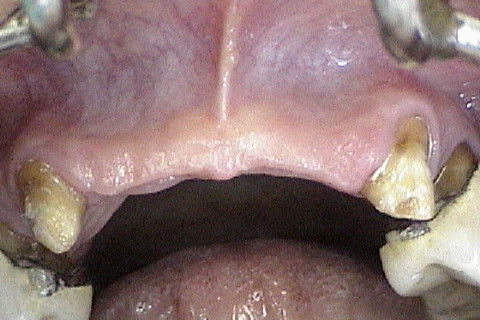

Aspecto clinico da região anterior maxilar, após remoção das proteses antigas